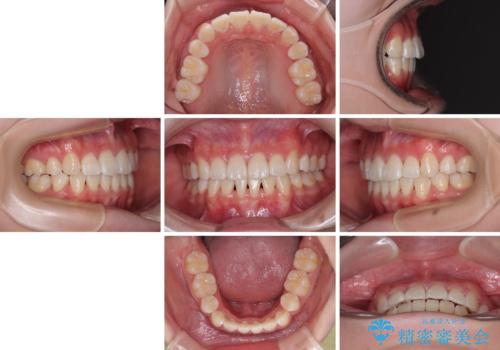

- 前歯がくちばしのように飛び出していることを気にして来院された患者様です。

唇が前方に突出している横顔が気になっているため、上下左右の第一小臼歯4本を抜歯し、ワイヤー装置にて矯正治療を行うこととしました。

わずか2年弱で一気に口元が変化し、患者様には大変満足していただけました。